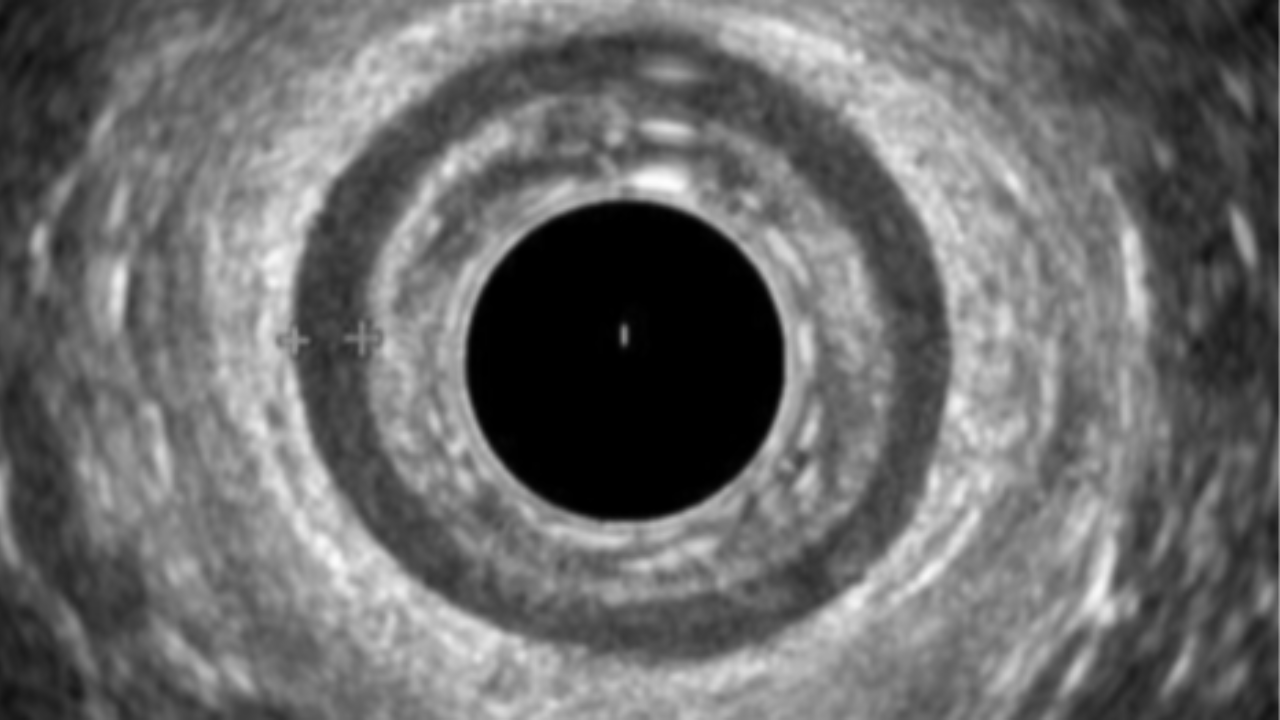

This 10-session live online mentorship programme will take you through a tried and tested fellowship where we will discuss indications, technique, interpretation and limitations of pelvic floor diagnostics, including; 1. Endoanal Ultrasound 2. Fluoroscopic Defecating Proctogram  3. MRI Defecating Proctogram 4. Anorectal Manometry The sessions will be designed to work with your busy schedule in mind and can be used weekly over a 12 week period or monthly over a 12 month period depending on the users learning needs and availability. Each session will comprise of teaching cases with short lectures exploring the visualised pathology and you can expect to see 100+ cases. A formative diagnostic imaging assessment will allow you to gain a certificate of completion, with a defined scope of practice, which you can be used to apply for your own departmental competency sign off.  You will also be asked to share anonymised examples of your own cases with your report to ensure your practice is at a high quality standard. The Ultrasound component of the material has been endorsed by the British Medical ultrasound Society and the additional modalities will be awarded credits in line with the Royal College of Radiologists accreditation scheme. This fellowship covers the essentials for any healthcare practitioner working with patients suffering with pelvic floor symptoms and aims to standardise your learning and give you access to global key opinion leaders from the comfort of your clinic. Please note spaces are limited so please enquire promptly to avoid disappointment. We look forward to hearing from you!

You will gain access to the Pelvic floor imaging Course, Community and Three one-on-one mentorship sessions with a Consultant Radiologist. ๐Ÿฉบ Master Pelvic Floor Imaging in 6 Weeks ๐Ÿฉบ  This course is suitable for healthcare professionals looking to increase knowledge of Pelvic floor imaging including: - Endoanal Ultrasound (EAUS) - Anorectal Manometry - Fluoroscopic Defecography - MRI Defecography What you'll get: You will gain INSTANT access to the community with weekly uploaded cases! Understand the indications and technique of performing these investigations Become proficient in Normal anatomy  Gain a comprehensive interpretation technique Explore a range of pathological cases  Gain an understanding of how to interpret Fluoroscopic and MRI Defecography  A Consultant-Led Online Course for Pelvic Floor Healthcare professionals โœ… Course Overview: ๐Ÿ” Week 1 & 2 : On-Demand Module with Live webinar โ€” Endoanal Ultrasound  ๐Ÿ”  Week 3: On-Demand Module with Live webinar  - Anorectal Manometry ๐Ÿ”  Week 4: On-Demand Module with Live webinar  - Fluoroscopic DPG ๐Ÿ”  Week 5: On-Demand Module with Live webinar  - MRI Defecating proctogram ๐Ÿง  Week 6: On-Demand Module with Live webinar  - Consolidate a Multimodality Approach to Pelvic Floor Imaging - Final Quiz + with Live interpretation Session Join weekly live sessions covering real clinical cases using: Endoanal Ultrasound (EAUS) Anorectal Manometry Fluoroscopic DPG MRI Proctogram Each session includes guided interpretation, Q&A with consultant radiologists, and key takeaways you can apply immediately. Test your skills and reinforce your learning with a structured quiz followed by a live image interpretation discussion. ๐Ÿ’ก What Youโ€™ll Gain ๐Ÿ’ก  Confidence in reading pelvic floor imaging Hands-on learning with real cases Direct mentorship from expert consultant radiologists Access to the pelvic Floor Academy Community CPD/CME accreditation ๐Ÿ–ฅ๏ธ Course Format: 100% Online โ€“ Join from anywhere Live sessions + On-Demand Access Recordings available after each session Interactive community inside Kajabi ๐Ÿ“…  Course Start Date: 07th March 2026 Spots are limited to ensure an interactive learning experience. You will gain INSTANT access to the community with weekly uploaded cases! This course is intended to give the theoretical knowledge necessary to understand pelvic floor imaging and acts as a theoretical aid your clinical practice. CPD Accredited This community is a place to: ๐Ÿ”น Share knowledge and learn together ๐Ÿ”น Analyse real-world cases and imaging scenarios ๐Ÿ”น Stay up to date with the latest techniques and guidelines ๐Ÿ”น Collaborate and connect with peers across multiple disciplines We have helped over 500+ healthcare professionals across the UK, Europe and Middle east working in; Radiology, Obstetrics and Gynaecology, Uro-gynaecology, Colorectal surgery, Gastroenterology and Physiotherapy gain a higher level of understanding of the technique and interpretation of pelvic floor investigations.   What you will get access to: ๐Ÿ”น Weekly Case uploads with expert interpretation ๐Ÿ”น Expert moderators will comment on your uploaded cases ๐Ÿ”น Monthly detailed videos of real-world cases ๐Ÿ”น Monthly Live webinars covering imaging interpretation ๐Ÿ”น Webinars will be recorded for on-demand access ๐Ÿ”น Access to a growing Case library of pelvic floor imaging cases   Each week, weโ€™ll be posting a new case for you to review and interpret, alongside monthly video explainers to aid your understanding. We encourage you to ask questions, contribute your insights, and grow alongside your colleagues. If this looks like the right place for you then we can't wait to meet you!

๐Ÿฉบ Master Pelvic Floor Imaging in 6 Weeks ๐Ÿฉบ  This course is suitable for healthcare professionals looking to increase knowledge of Pelvic floor imaging including: - Endoanal Ultrasound (EAUS) - Anorectal Manometry - Fluoroscopic Defecography - MRI Defecography What you'll get: You will gain INSTANT access to the community with weekly uploaded cases! Understand the indications and technique of performing these investigations Become proficient in Normal anatomy  Gain a comprehensive interpretation technique Explore a range of pathological cases  Gain an understanding of how to interpret Fluoroscopic and MRI Defecography  A Consultant-Led Online Course for Pelvic Floor Healthcare professionals โœ… Course Overview: ๐Ÿ” Week 1 & 2 : On-Demand Module with Live webinar โ€” Endoanal Ultrasound  ๐Ÿ”  Week 3: On-Demand Module with Live webinar  - Anorectal Manometry ๐Ÿ”  Week 4: On-Demand Module with Live webinar  - Fluoroscopic DPG ๐Ÿ”  Week 5: On-Demand Module with Live webinar  - MRI Defecating proctogram ๐Ÿง  Week 6: On-Demand Module with Live webinar  - Consolidate a Multimodality Approach to Pelvic Floor Imaging - Final Quiz + with Live interpretation Session Join weekly live sessions covering real clinical cases using: Endoanal Ultrasound (EAUS) Anorectal Manometry Fluoroscopic DPG MRI Proctogram Each session includes guided interpretation, Q&A with consultant radiologists, and key takeaways you can apply immediately. Test your skills and reinforce your learning with a structured quiz followed by a live image interpretation discussion. ๐Ÿ’ก What Youโ€™ll Gain ๐Ÿ’ก  Confidence in reading pelvic floor imaging Hands-on learning with real cases Direct mentorship from expert consultant radiologists Access to the pelvic Floor Academy Community CPD/CME accreditation ๐Ÿ–ฅ๏ธ Course Format: 100% Online โ€“ Join from anywhere Live sessions + On-Demand Access Recordings available after each session Interactive community inside Kajabi ๐Ÿ“…  Course Start Date: 07th March 2026 Spots are limited to ensure an interactive learning experience. You will gain INSTANT access to the community with weekly uploaded cases! This course is intended to give the theoretical knowledge necessary to understand pelvic floor imaging and acts as a theoretical aid your clinical practice. CPD Accredited